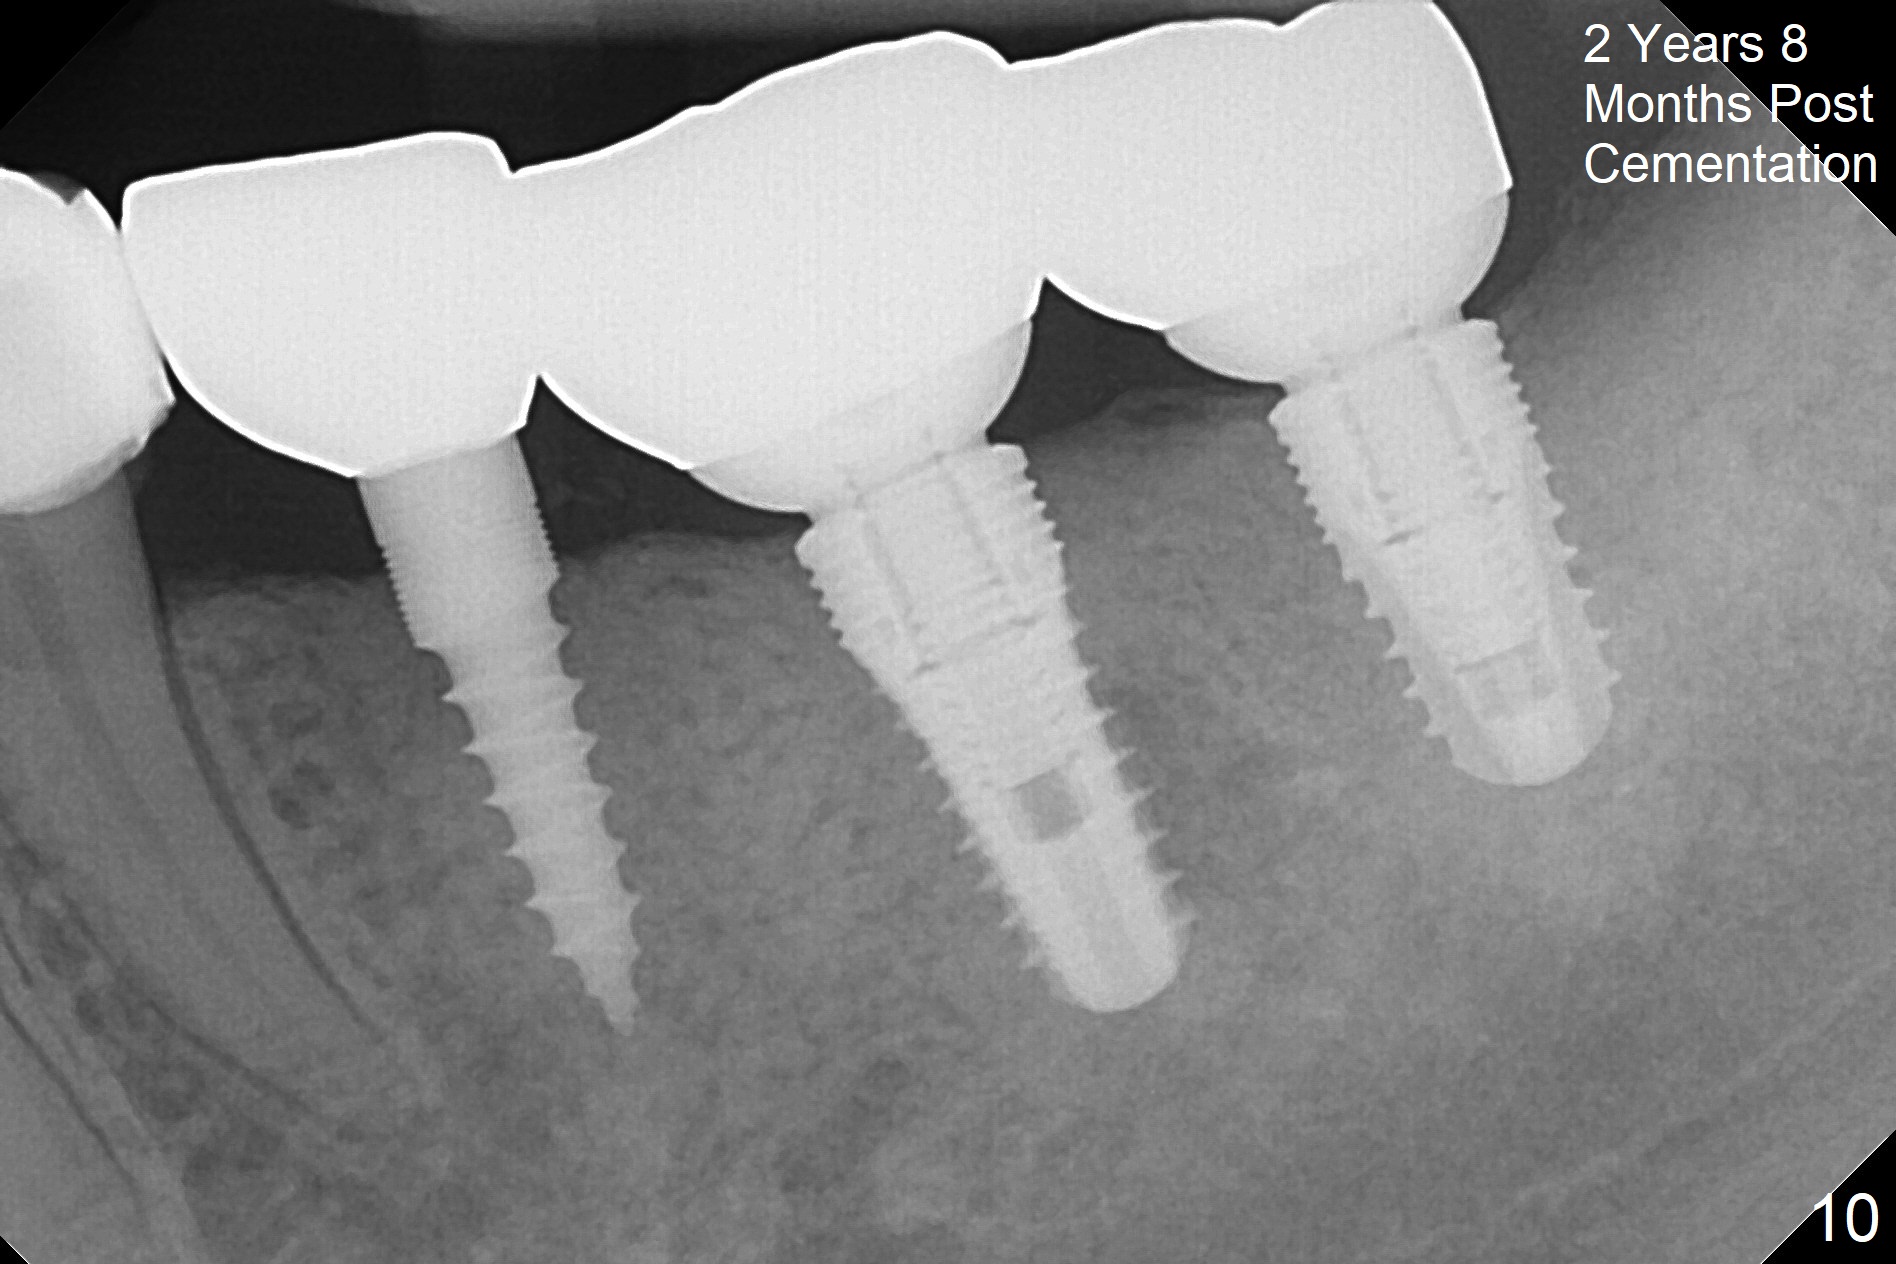

The patient is doing well postop, but 1 month postop, she complains of pain in the left submandibular area. When the immediate provisional is removed, the gingiva between the implants is erythematous (Fig.5 ^). The provisional is modified with accentuated grooves between the margins of the implants (Fig.6 *) with oral hygiene instruction. In fact the provisional is not cemented so that it is easy for self cleansing. There is crestal bone resorption 3 months postop (Fig.7,8). No further bone loss 1 year post cementation (Fig.9, cropped from pan). The bone density around the implants increases 2 years 8 months post cementation (Fig.10).